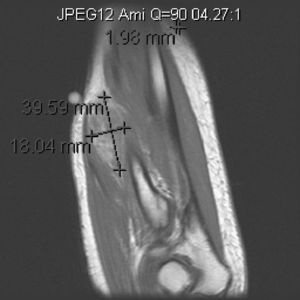

Mujer de 73 años con antedecente de melanoma coroideo en ojo derecho en 1999 tratado con braquiterapia. En mayo de 2008 acudió por nódulo en antebrazo izquierdo de 4 meses de evolución. A la exploración física se objetivaba un nódulo no doloroso a la palpación que parecía depender de la musculatura extensora. El hemograma, la bioquímica y el examen de orina fueron normales. La VSG de 26mm (0–20). La Rx del antebrazo (fig. 1) evidenció una masa densa en partes blandas sin erosión ósea. La ecografía (fig. 2) objetivó una tumoración ovalada, sólida con flujo arterial en su interior. La RM (fig. 3) mostró una masa sólida hiperintensa en T1, levemente hiperintensa en T2 y algo más brillante en STIR.

Hay muy pocos casos publicados de metástasis musculares procedentes de melanomas malignos5–7. La manifestación clínica habitual consiste en una masa dolorosa localizada con mayor frecuencia en músculo psoas, iliopsoas, musculatura paravertebral y proximal de los miembros8. En la RM la señal hiperintensa en T1, debida al efecto paramagnético de la melanina, es un signo característico de esta entidad5. El diagnóstico de certeza es anatomopatológico. De todo lo dicho anteriormente, se desprende que siempre se debe tener en cuenta los antecedentes personales del paciente, sobre todo en el caso de neoplasias.